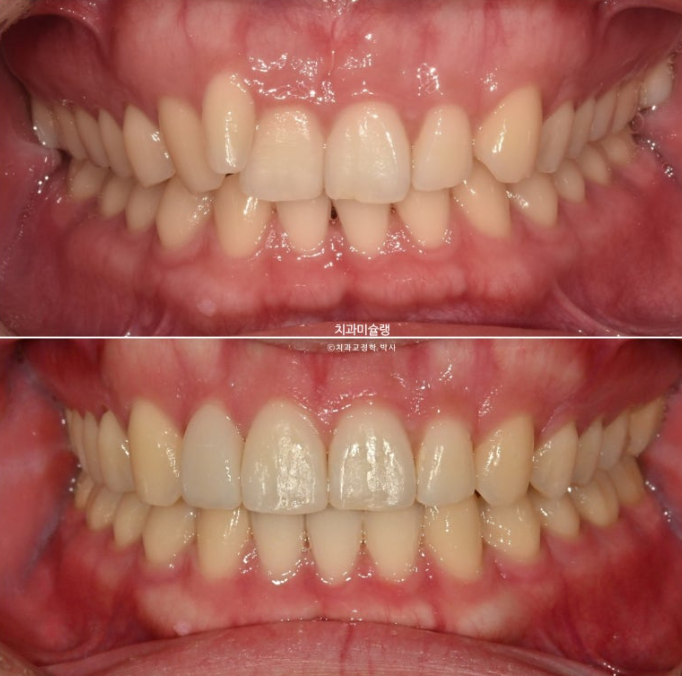

차례대로 교정 완료 직후 - 무삭제 라미네이트 부착 후 - 앞니 끝단 레진 치료 후 사진 입니다.

25년 11월 라미네이트 레진 등 보철을 포함한 모든 치료를 마무리 했습니다.

25.11

이제 전 후 비교 보겠습니다.

24.03~25.11

옥니의 개선으로 미소가 환해졌습니다.